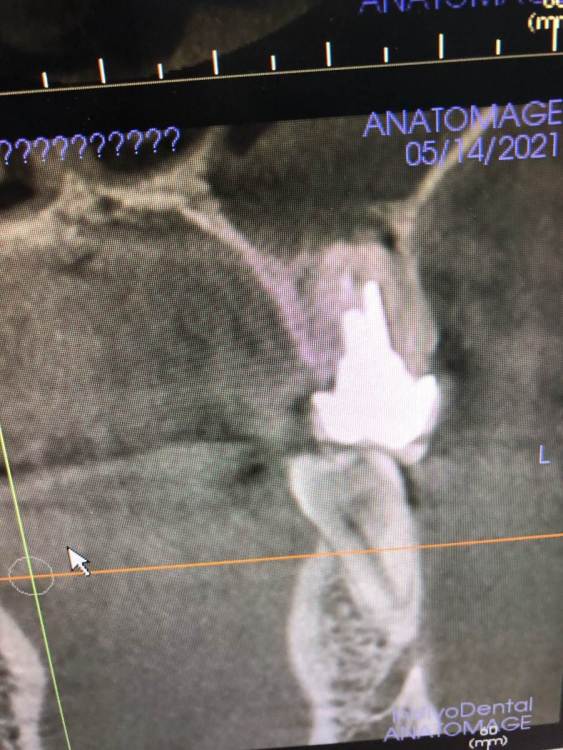

gw000 Опубликовано 14 мая, 2021 Поделиться Опубликовано 14 мая, 2021 Здравствуйте. Сильная боль при надавливании на 25 зуб, в нем два штифта в каналах а сверху коронка. Диагноз «киста». Предложено лечение - удаление и установка имплантата. Специалист мотивировал выбор этой тактики тем, что после извлечения штифтов и последующих манипуляций каналы станут слишком широкими и возможности повторно поставить штифты уже не будет. А также упомянул что имплантант будет поставить проще и дешевле. Мотивация пациента проста - как можно дольше сохранить зуб на месте и избежать как минимум установки имплантат а максимум удаления. Возможно ли терапевтическое лечение без удаления с последующей установкой штифтов и коронки или предложите пожалуйста иные варианты? Ссылка на комментарий

St. Опубликовано 14 мая, 2021 Поделиться Опубликовано 14 мая, 2021 По снимку штифты объемные. Если хотите попробовть побороться за зуб, то можно снять коронку , достать штифты и оценить что осталось от зуба. Если стенок достаточно - то перелечивать каналы и делать новый штифт и коронку, если недостаточно - то удалять и имплант. Но нужно найти квалифицированного эндодонтиста, т.к. если будет перелечивание то работа сложная и ювелирная. Альтернатива - удаление. Ссылка на комментарий

АнтонТЛТ Опубликовано 14 мая, 2021 Поделиться Опубликовано 14 мая, 2021 Резекцию с ретроградной пломбировкой можно ещё рассмотреть. Ссылка на комментарий